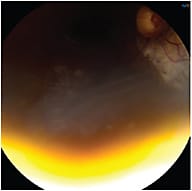

|

| Q. Is this an equipment operational problem? | A. Possibly; the camera may not be in alignment. |

| Q. What troubleshooting is needed for the camera? | A. Manipulate the camera angle to overcome this problem. |

| Q. Is there pathology present? | A. Yes. An elevated chorioretinal scar. |

| Q. What aberrations/artifacts are included and how do you correct them? | A. Lid artifact is present. If it was the iris, the artifact would be a bluish tint. A white crescent around the picture indicates the camera is too far away and not in focus. |

| COURTESY STEPHANIE D. MCMILLAN, MHA, COA | |